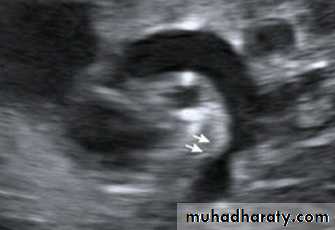

2-Echocardiography shows the site and degree of coarctation, presence of left ventricular hypertrophy, and aortic valve morphology and function

3-Echocardiography

The location and size of the atrial defect are readily appreciated by two-dimensional scanning . The shunt is confirmed by pulsed and color flow Doppler .